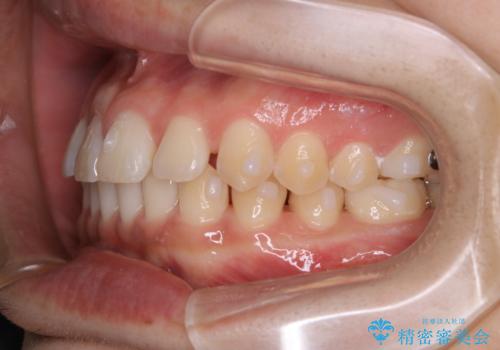

- 上のすきっ歯が気になるとご相談にいらした方です。上下顎ともにスペースがあったため、インビザラインFULLにて見た目と噛み合わせの改善も同時に行いました。

元々は上前歯のみの部分矯正をご希望されていましたが、下の歯もスペースがあり、噛み合わせ的にも上のみの部分治療は難しいことをお話ししました。前歯のみの部分矯正を行った場合、前歯の隙間だけが閉じて奥歯が噛めなくなってしまう場合もあります。インビザラインFULLにて治療することで、噛み合わせと見た目を同時に改善させることができ、大変喜んでいただけました。